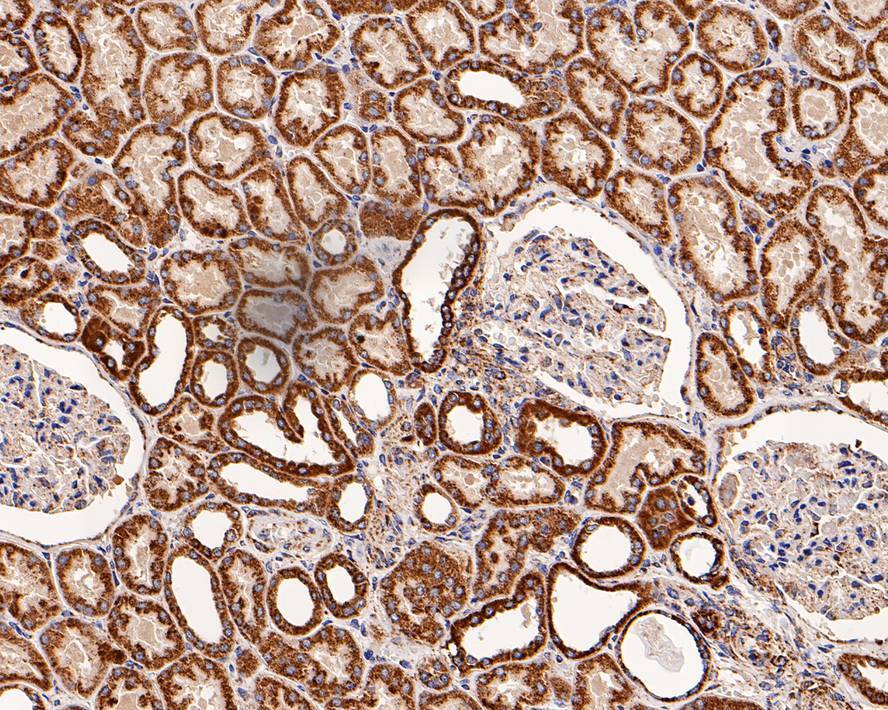

- Main image

- Experimental details

- Immunohistochemistry analysis of GC1q R in paraffin-embedded human kidney tissue. The section was pre-treated using heat mediated antigen retrieval with Tris-EDTA buffer (pH 9.0) for 20 minutes. The tissues were blocked in 1% BSA for 20 minutes at room temperature, washed with ddH2O and PBS, and then probed with GC1q R Monoclonal antibody (Product # MA5-44926) using a dilution of 1:1,200 for 1 hour at room temperature. The detection was performed using an HRP conjugated compact polymer system. DAB was used as the chromogen. Tissues were counterstained with hematoxylin and mounted with DPX.